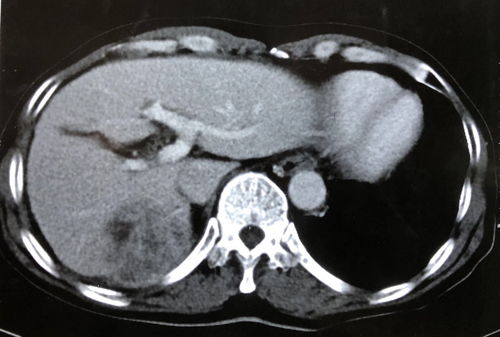

对于肝癌,B超有其典型的影像学表现,如低回声或混合回声团块、边界不规则、周边有声晕、内部血流信号丰富(“快进快出”的增强模式在超声造影中更明显)等。对于直径超过1-2厘米的肝癌结节,B超具有较高的检出率。

增强CT/MRI:通过观察病灶在动脉期、门脉期和延迟期的强化特征(典型的HCC表现为“快进快出”——动脉期明显强化,门脉期或延迟期强化消退),可以极大提高诊断的准确率。MRI对于小肝癌和肝硬化结节的鉴别能力通常优于CT。